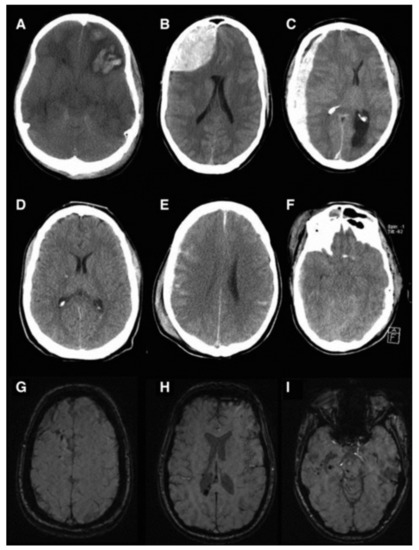

| Injury Severity | Injury Mechanism | Presence of MEI | Imaging Characteristics | Animal Models |

|---|---|---|---|---|

| Mild Upper Intermediate | Diffuse Blunt Force Trauma Fall Sports Injury Rotational Acceleration of Brain | No | Cerebral Edema Concussion Grade 1 DAI No Presence of Lesion or Cortical Tissue Loss | CHIMERA Modified Marmarou Modified CCI Weight Drop (Marmarou) Midline FPI |

| Lower Intermediate | Fall RTI Focal Blunt Force Trauma | Possible | Diffuse Cortical Contusion Intraventricular Hemorrhage Subarachnoid Hemorrhage | Weight Drop (Shohami and Marmarou) CCI Blast Injury Lateral FPI |

| Severe | Focal Penetration Laceration GSW | Probable | Skull Fracture Focal Cortical Contusion Cortical Tissue Loss Cavity Formation Subdural Hematoma Epidural Hematoma | Weight Drop (Feeney and Shohami) CCI Lateral FPI PBBI |